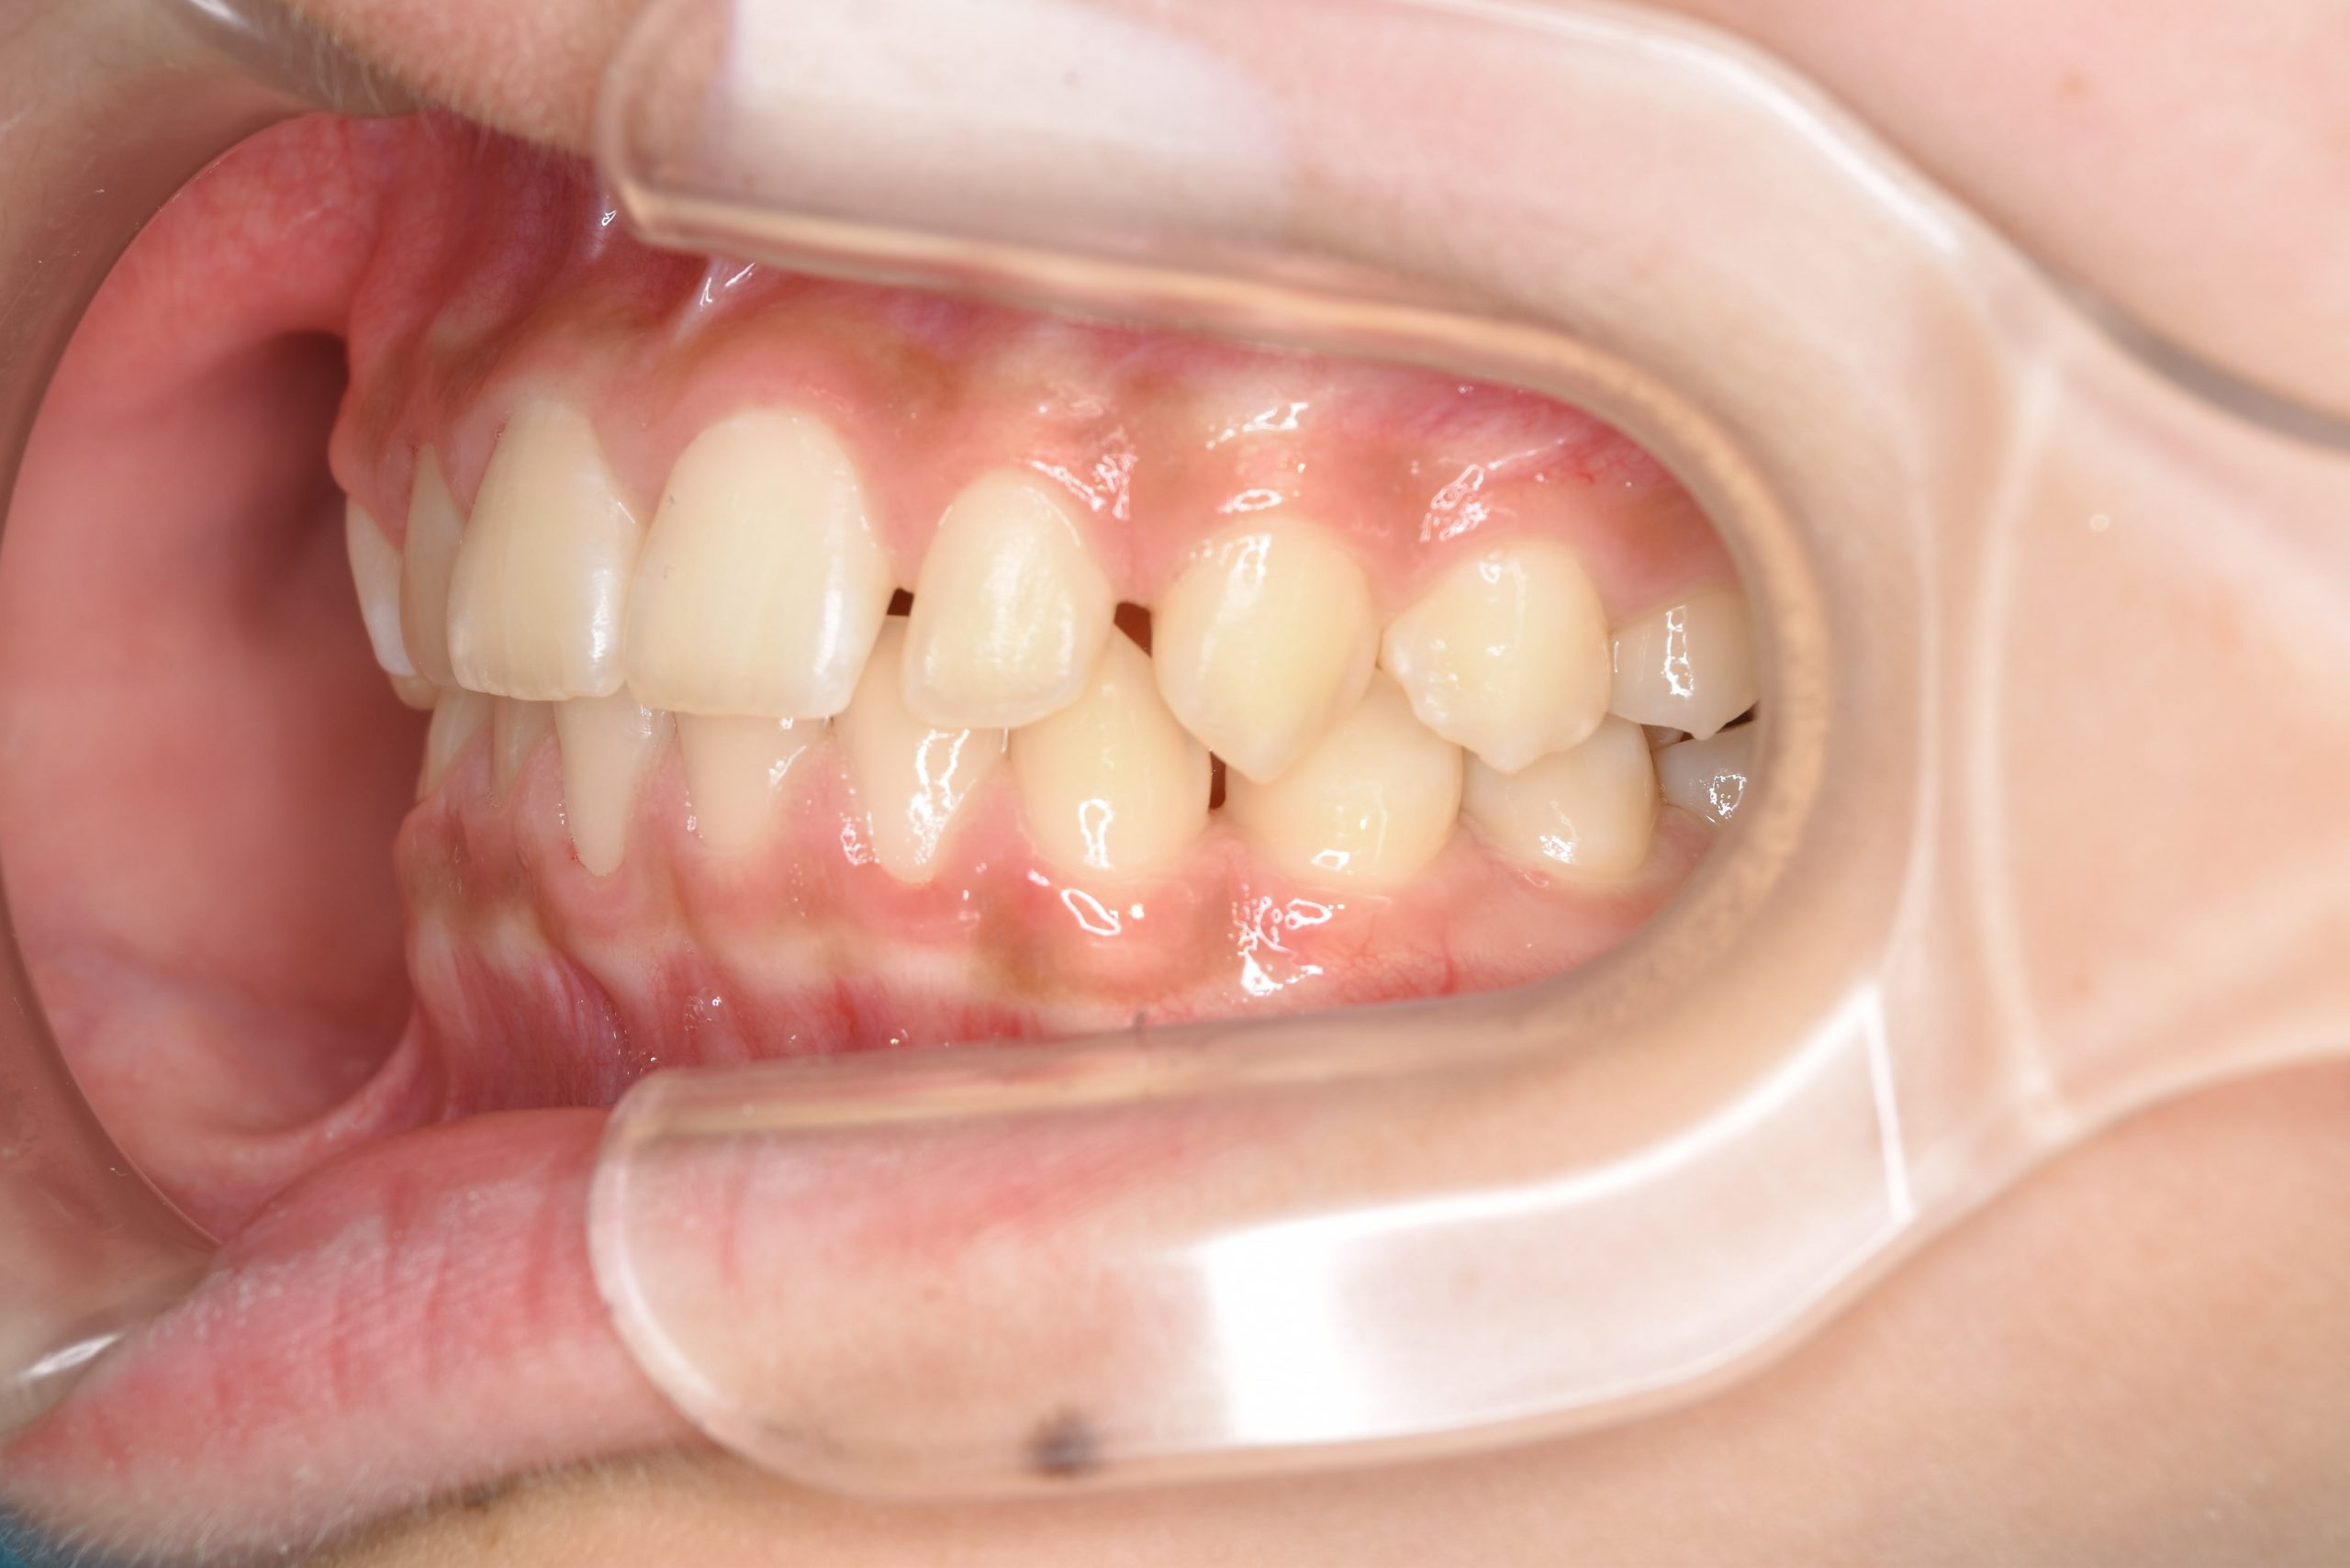

ビフォー

全顎ワイヤー矯正 症例_108

主訴 受け口|前歯がかみ合わない|顔貌

施術内容 小児矯正1期治療

治癒期間 3年11ヶ月間

費用 498,960円(税込)

リスク・副作用 違和感、不快感、痛み